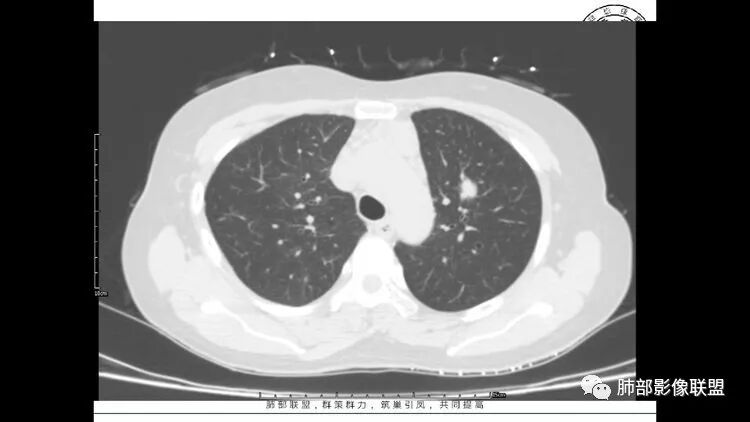

老年女性,长期使用激素史。双肺多发散在斑片状磨玻璃密度影及大小不等的薄壁含气囊腔,下肺相对较多较大。双肺多发结节,左肺上叶结节相对较大,界清,边缘光滑,分叶不明显。右肺下叶前外底段散在树丫。前上纵膈偏左侧不规则软组织团块,颗粒感,偏软。肺内囊腔及磨玻璃影考虑淋巴细胞间质性肺炎,或淋巴管肌瘤病。纵膈团块考虑淋巴管瘤。两者结合,考虑淋巴细胞增生病变。右肺下叶散在树丫,结核待排。双肺结节性质待定。

双肺多发散在斑片状磨玻璃密度影及大小不等的薄壁含气囊腔,下肺相对较多较大。双肺多发结节,界清,边缘光滑,分叶不明显。右肺下叶前外基底段散在斑片树芽。前上纵膈偏左侧不规则软组织团块,密度不均,其内可见不规则纤维样低密度,周围簇状小淋巴结。考虑1淋巴细胞间质性肺炎。2考虑纵膈胸腺淋巴瘤。

双肺下叶分布为主的间质改变(磨玻璃影、小叶间隔增厚)、散在气囊影(常有血管贴边)、边界不清小结节